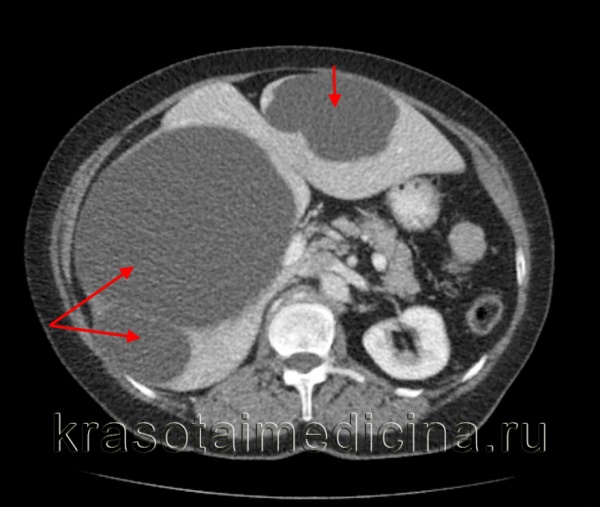

- УЗИ или КТ органов брюшной полости могут помочь определить наличие кисты и её размеры.